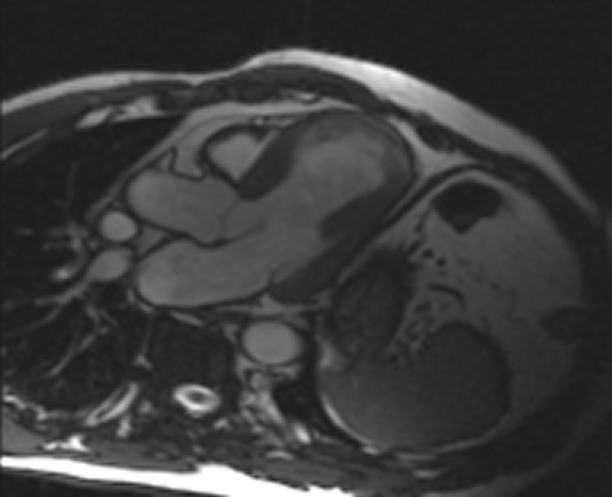

RM Cardíaca

Descripción

Es una prueba diagnóstica no invasiva que obtiene información morfológica y funcional del corazón y las estructuras adyacentes; de esta manera se pueden diagnosticar diferentes patologías congénitas y adquiridas, o bien realizar controles en pacientes con patología previa ya conocida. En la gran mayoría de casos es necesario el uso de contraste intravenoso (gadolinio) para completar el estudio, un tipo de contraste que raramente produce reacciones adversas. Durante la prueba, el técnico le pedirá varias veces que aguante la respiración durante 10-15 segundos para obtener las imágenes lo más claras posible. No se necesita preparación previa alguna por parte del paciente. La duración de la prueba es de aproximadamente 45-60 minutos. Está contraindicada en pacientes con marcapasos; el paciente debe avisar si es portador de implantes metálicos y/o clips quirúrgicos.